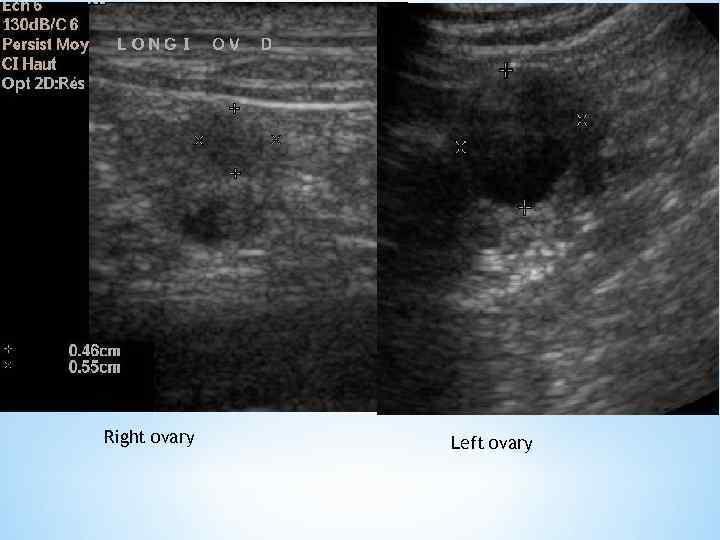

Right ovary Left ovary